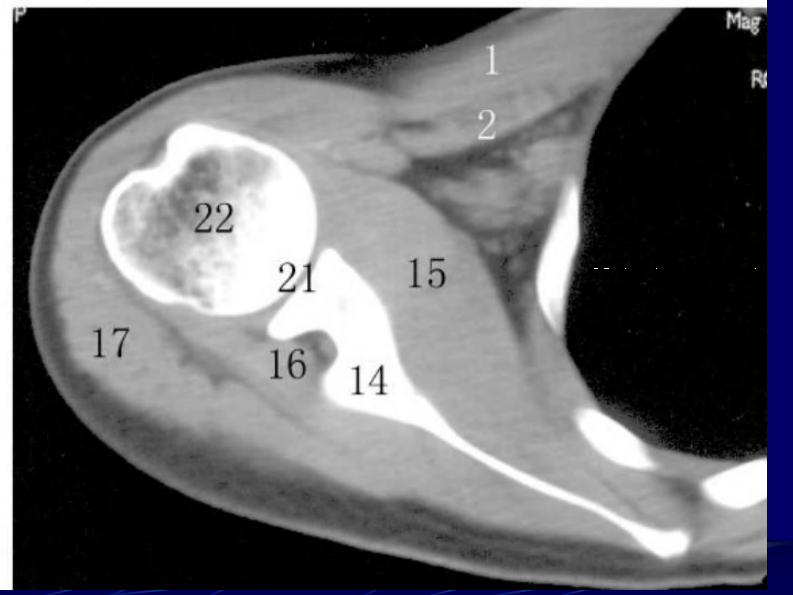

14 四肢断层解剖及CT、MRI.pdf